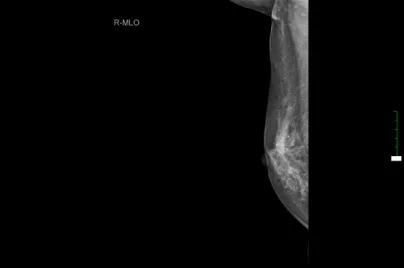

现病史:患者3年余前无意中发现右乳头后方有一肿块,约“枣样”大小,皮肤略红肿,无糜烂,乳头无溢血溢液,就诊于当地医院,建议定期复查处理。3年余来肿块逐渐增大,现约如“核桃样”大小,皮肤“橘皮样”变伴红肿,无发热,遂就诊于淮阳县人民医院,行乳腺彩超示:右乳实性占位(36x15mm),行乳腺钼钯示:右侧乳腺高密度块状影(2.9cmx4.0cm),建议进一步检查。今患者为求进一步诊治来我院就诊,门诊诊断为:“右乳肿块:乳腺癌?”,建议进一步治疗,遂收入院。

辅助检查

双乳彩超:右乳低回声肿块,BI-RADS 4C类,右侧腋窝淋巴结增大。

胸部CT: 1、右侧乳腺区占位并右侧腋窝、右侧胸大肌内侧多发淋巴结肿大。2、纵隔淋巴结可见,个别肿大。3、双肺临近肺底区炎性机化性改变。4、右侧肾上腺局部占位。